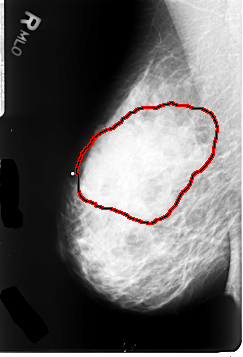

FILE: B_3061_1.RIGHT_CC.OVERLAY

TOTAL_ABNORMALITIES 1

ABNORMALITY 1

LESION_TYPE CALCIFICATION TYPE PLEOMORPHIC DISTRIBUTION REGIONAL

LESION_TYPE MASS SHAPE FOCAL_ASYMMETRIC_DENSITY MARGINS N/A

ASSESSMENT 4

SUBTLETY 3

PATHOLOGY MALIGNANT

TOTAL_OUTLINES 1

BOUNDARY